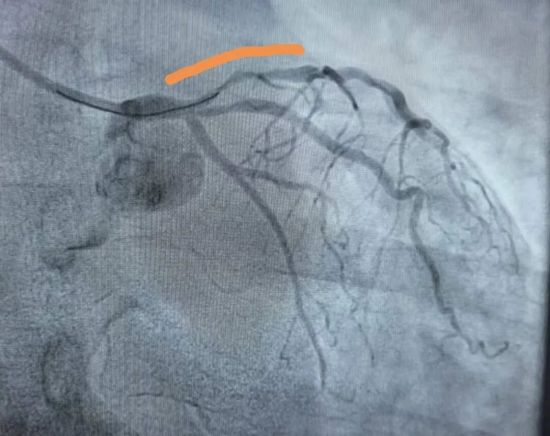

术后LAD血管开通,择期介入治疗

患者术后房颤,抬高的ST段回落